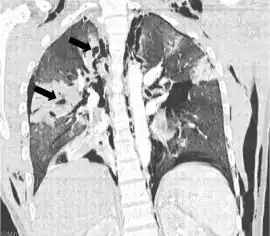

TC coronal que muestra radiolucencias (áreas pálidas en la radiografía) en el pulmón causadas por laceraciones pulmonares ubicadas a la izquierda de la imagen (flechas negras) | ||

La laceración pulmonar puede no ser visible utilizando radiografía de tórax porque una contusión pulmonar asociada o hemorragia lo puede ocultar. Cuando la contusión pulmonar aclara (normalmente dentro dos a cuatro días), las laceraciones comienzan a ser visibles en la radiografía de tórax.[14] Una TAC es mejor detectando laceraciones pulmonares que una radiografía de tórax,[15] y a menudo revelan múltiples laceraciones en casos donde radiografía de pecho mostró solo un contusión. Antes de que las TAC estuvieran disponibles masivamente, la laceración pulmonar era considerada poco usual debido a que no era común encontrarlas en las radiografías. En una TAC las laceraciones pulmonares aparecen en un área contusa del pulmón,[16] típicamente apareciendo como las cavidades llenas de aire o fluido[17] que normalmente tener una forma circular u ovoide debido a la elasticidad del pulmón.